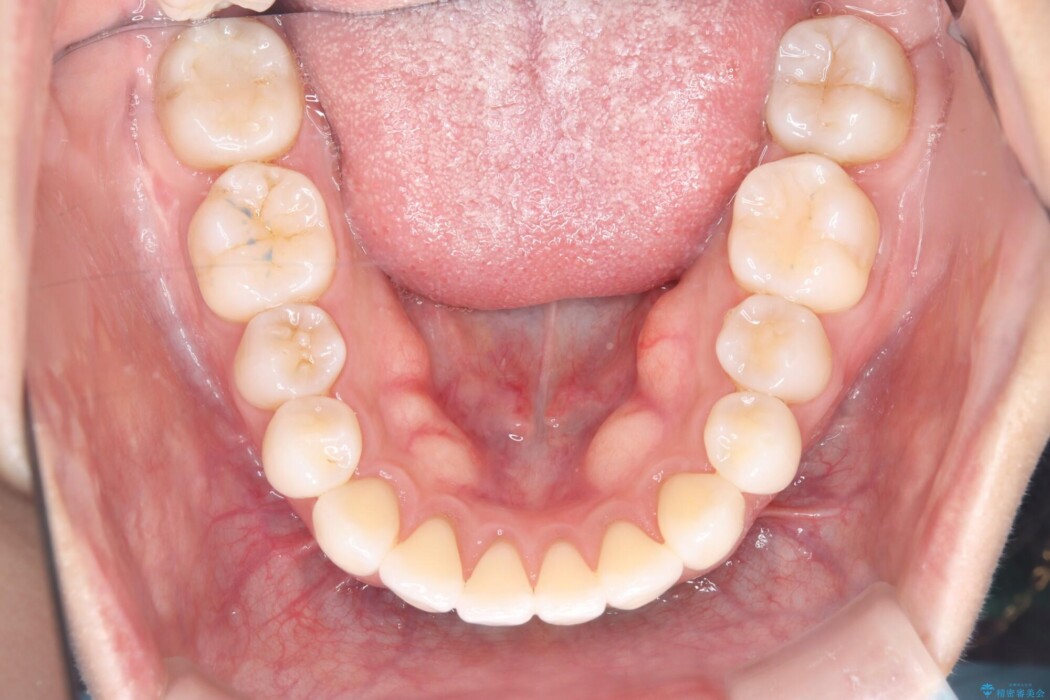

治療完了後、前歯のガタつきはきれいに整い、上下の奥歯も理想的な位置で噛み合うようになりました。非抜歯での治療により、ご自身の歯をすべて残したまま、機能的で美しい歯並びを実現することができました。